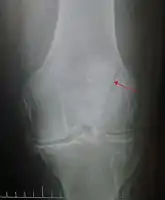

Transverse fracture of patella